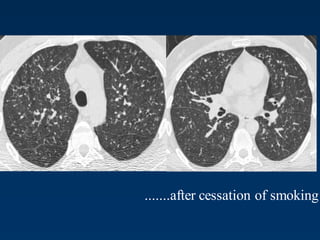

1 year later

Peribronchiolar Nodules Cavitating nodules and cysts

Langerhans Cell Histiocytosis

Langerhans Cell Histiozytosis

Key Features

Upper lobe predominance

Combination of cysts and noduli

Characteristic stages

Increased Lung volume

Sparing of costophrenic angle

.......after cessation of smoking